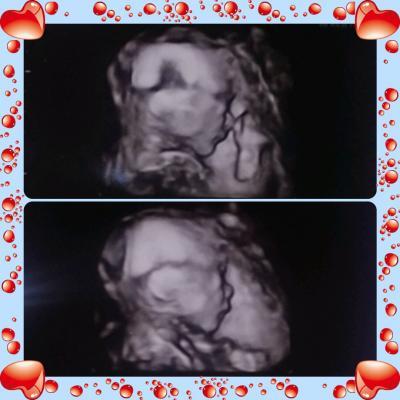

So bei meinen kleinen Sohn ist alles io. Alles dran und alles funktioniert einwandfrei, nur zeigen wollte er sich nicht von vorn... Er hat mit seinem Köpfchen ganz tief in meinem Becken gelegen. Er ist 21cm groß und 363g schwer...

Bild zu zurück von der Feindiagnostik - Forum für Januar - Mamis

Sehr süß , ein kleines Wunder...